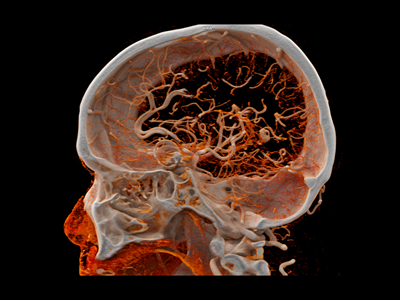

CT (Computed Tomography) Scans

Computed Tomography (CT) scans are a type of medical imaging that provide detailed pictures of the inside of your body. Unlike regular X-rays, CT scans use advanced technology to create cross-sectional images of bones, organs, and tissues. These images help doctors diagnose and monitor a wide range of conditions—from injuries and infections to cancer and heart disease.

In short, a CT scan gives your care team a clear, layered view of what’s happening inside your body, helping them make accurate and timely decisions about your health.